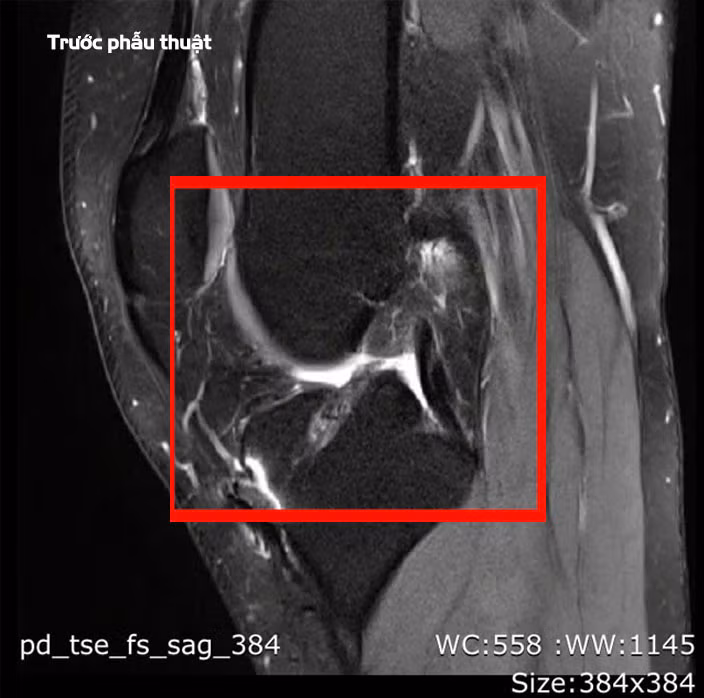

BSCKII Lê Hoàng Văn Hải, Trưởng khoa Chấn thương Chỉnh hình cho biết, qua thăm khám lâm sàng và chụp MRI, chúng tôi xác định bệnh nhân bị đứt hoàn toàn dây chằng chéo trước. Với trường hợp phẫu thuật lần thứ ba này, ê-kíp đã lựa chọn phương pháp tái tạo bằng gân hamstring kết hợp kỹ thuật All-Inside để tăng kích thước mảnh ghép.

Ca phẫu thuật được thực hiện vào ngày 18/2, kéo dài 90 phút và diễn ra thuận lợi. Ê-kíp phẫu thuật đã xử lý triệt để phần dây chằng cũ và đường hầm xương cũ, đồng thời tái tạo mới nhằm tối ưu hóa khả năng liền gân và xương.

![]() |

| Tổn thương dây chằng trên phim chụp - Ảnh BVCC |